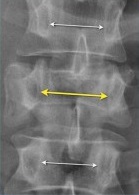

Distância interpedicular: É a distância entre os pedículos das vértebras. Nesta situação os pedículos, pequenas protuberâncias das vértebras, servem como pontos de referência para medir a largura do canal espinal.